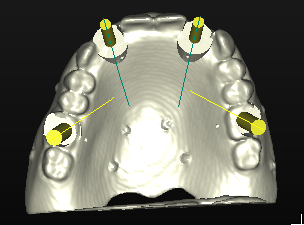

La pianificazione con Simplant permette l’accoppiamento tra la protesi e i tessuti molli oltre alla corretta valutazione della posizione, dell’inclinazione e dell’orientamento tridimensionale degli impianti (Figg. 15-17). Questo tipo di progettazione consente di eseguire una procedura chirurgica protesicamente guidata, sfruttando l’emergenza degli impianti nella loro più ideale posizione, con benefici dal punto di vista protesico e biomeccanico (Figg. 18, 19)

Grazie a questo tipo di pianificazione il software produce una guida chirurgica che viene stampata da una stampante 3D e consente al chirurgo di operare con tecnica “flapless” cioè senza la necessità di aprire dei lembi e causare un maggiore traumatismo al paziente. La guida chirurgica trasparente viene provata in bocca al paziente prima dell’intervento chirurgico per testare la sua stabilità e precisione nel rapporto con i tessuti molli (Figg. 20, 21). In questo caso specifico si era pianificato di utilizzare un nuovo approccio con degli impianti e componenti protesiche particolari, la tecnica “Smart fix” di Astra Tech Implant (Dentsply Sirona) (Figg. 22-25).